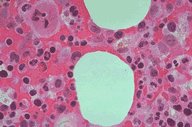

Set 3 Normal and Abnormal Bone Marrow Biopsies

Slide 4 of 192 Image ID 522

Normal marrow

A high dry power view of a normal bone marrow

specimen. Two megakaryocytes can be

appreciated, as can erythroid and myeloid

elements.